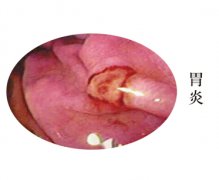

盘锦治疗肠炎要花多少钱

导语 肠炎不是普通炎症,发每年死于结肠癌的患者逐步上升,然而更多的肠炎

治疗肠炎哪家医院好

导读 【导语】 随着现在生活节奏的加快和工作压力的增加,肠炎患者人数日趋